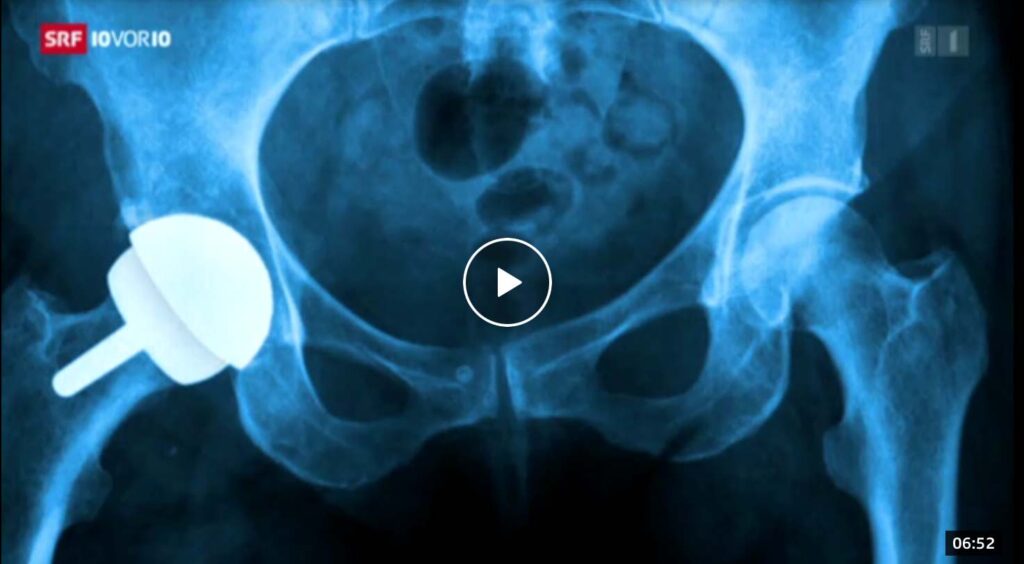

- SRF 10vor10, De Puy – Jetzt kommen die Klagen, Stephan Kinzl.